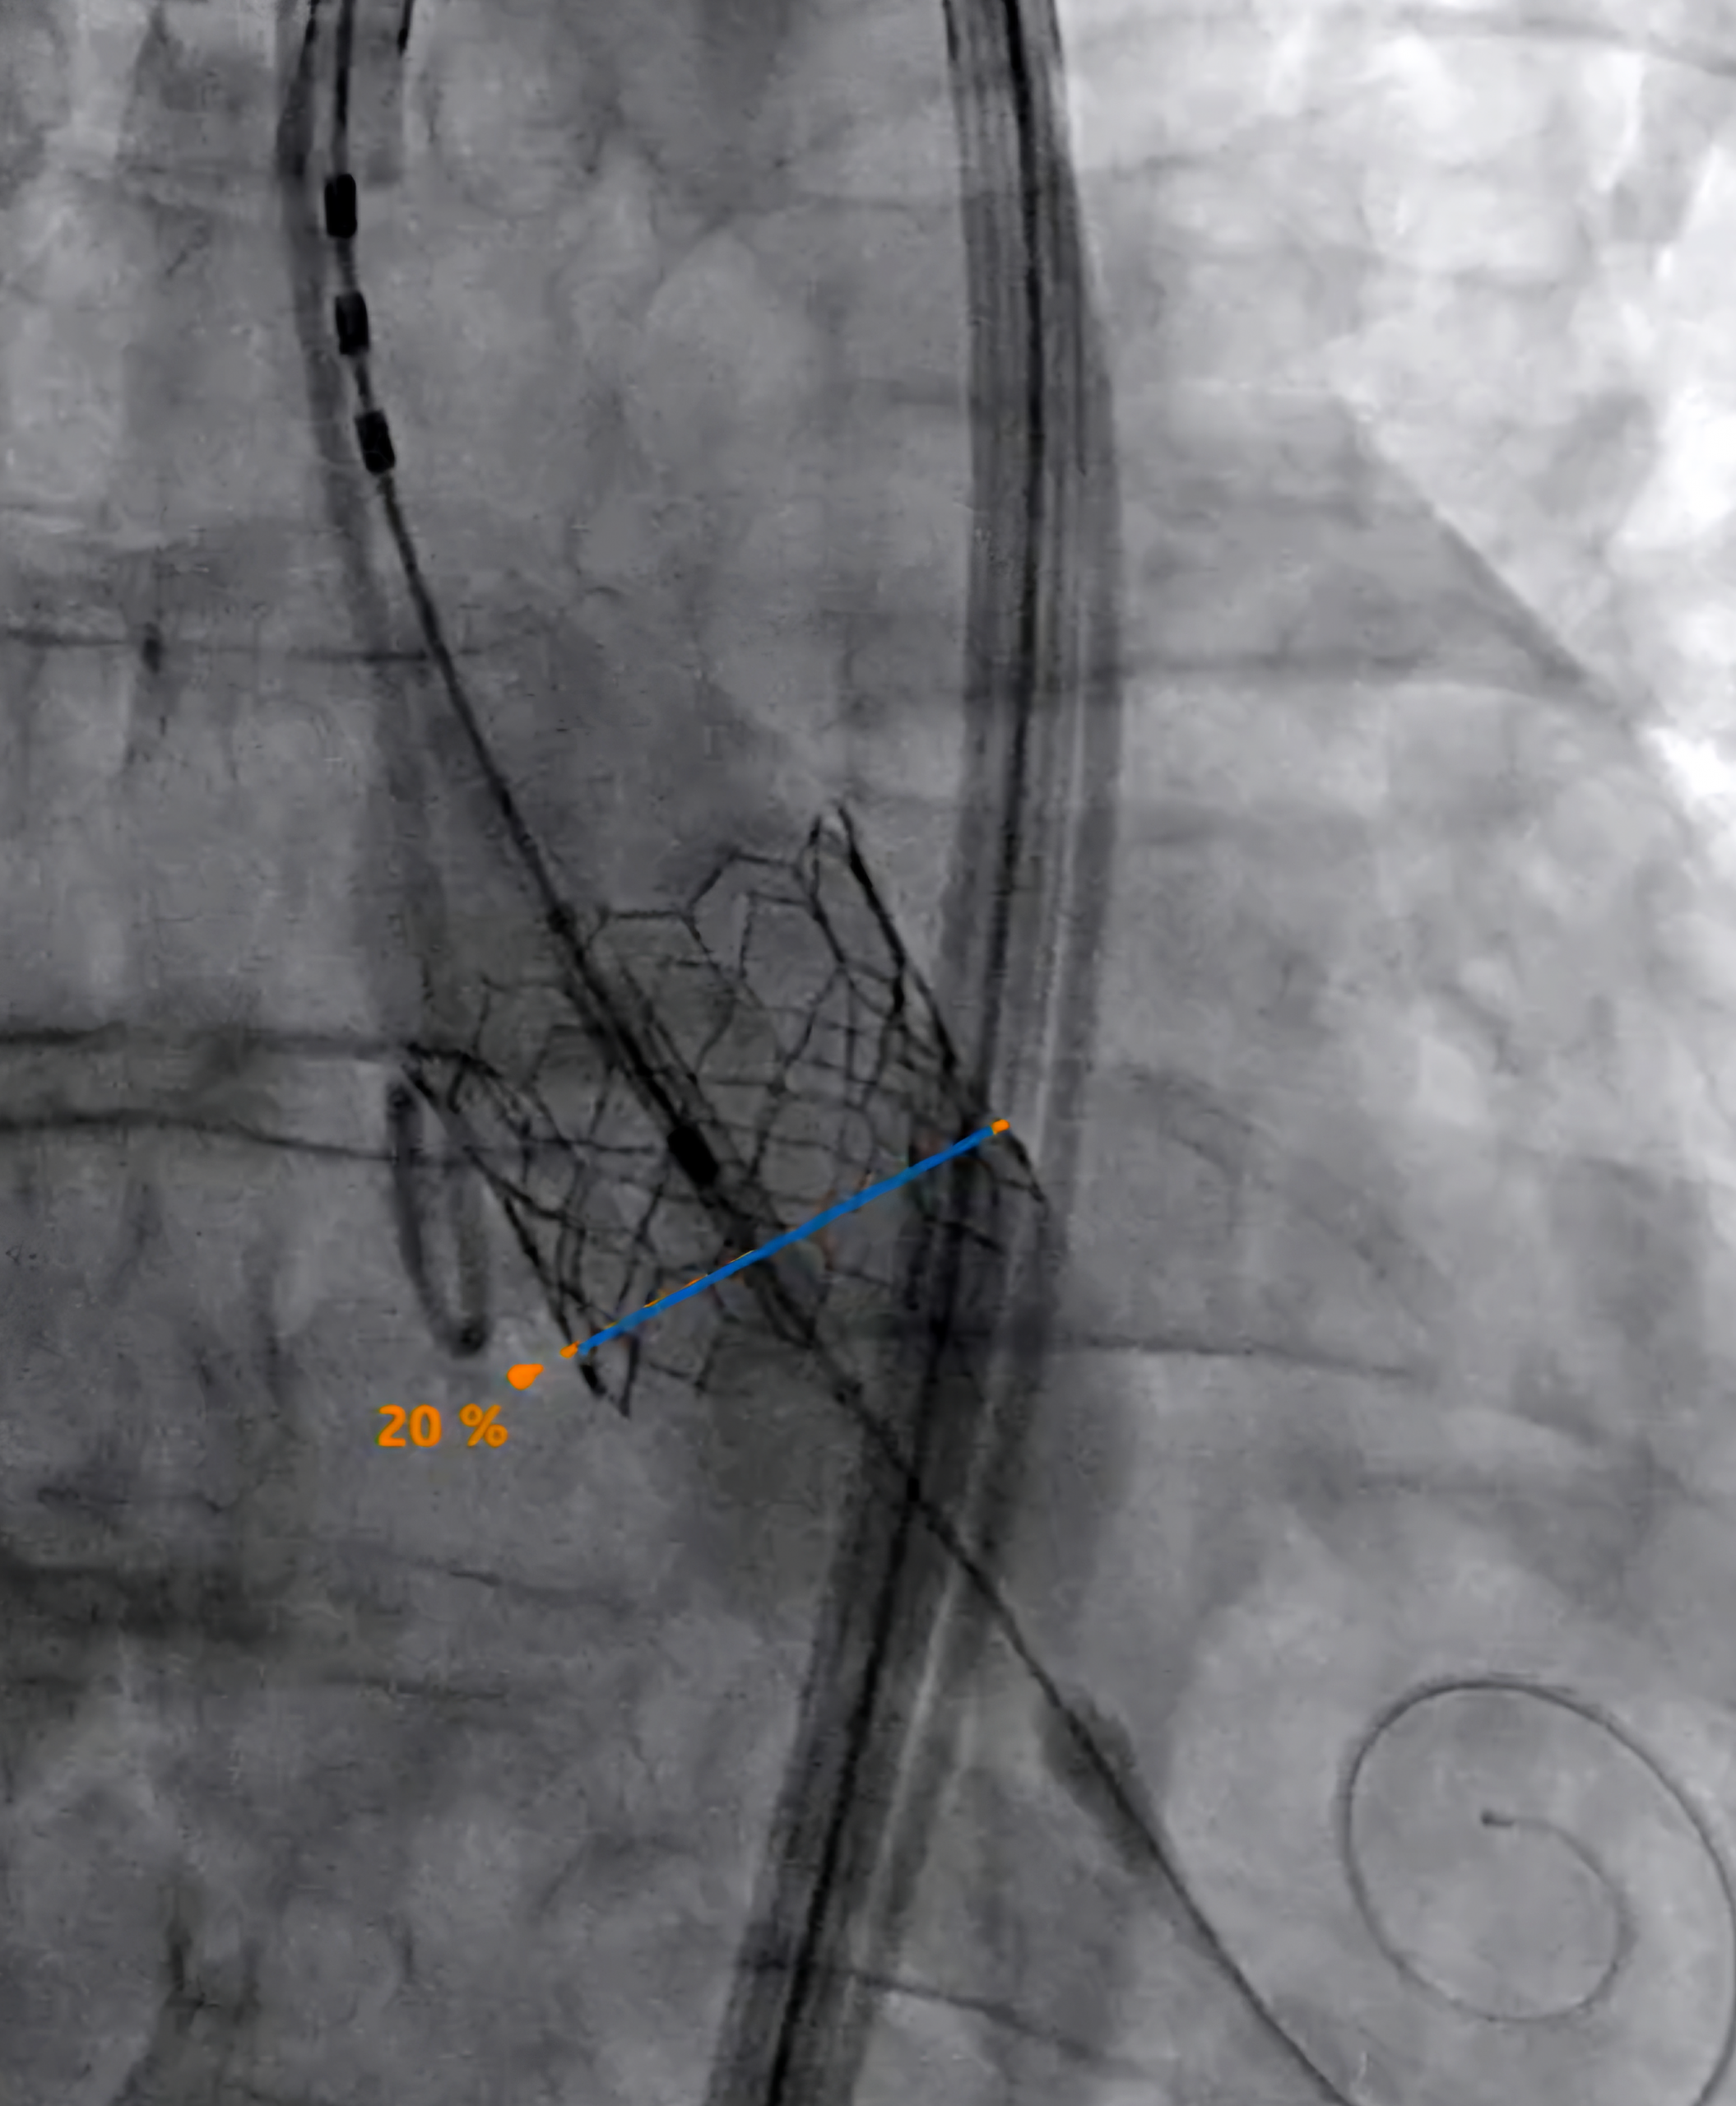

MITRA-PILOT combines advanced image guidance, AI, robotics, and the proprietary EPYGON biomimetic transcatheter mitral valve to autonomously deliver prosthetic mitral valve.

Epygon is the first “physiological” transcatheter mitral valve restoring the natural blood flow vortex in the left ventricle. It fosters recovery of ventricular function, especially in fragile patients with a seriously impaired cardiac condition.

By integrating AI guidance and robotic precision with biomimetic valve design, MITRA-PILOT aims to deliver a differentiated and physiologically optimized solution for mitral valve replacement.

Epygon makes it possible to generate blood flow closest to normal flow inside the left ventricle, avoiding in particular the stagnation of blood inside the ventricle. Furthermore, this asymmetrical valve, lower in height on the side where the left ventricle ejects, just under the aorta valve, optimizes the ejection function. It doesn’t impede the aortic valve, as with some other devices.